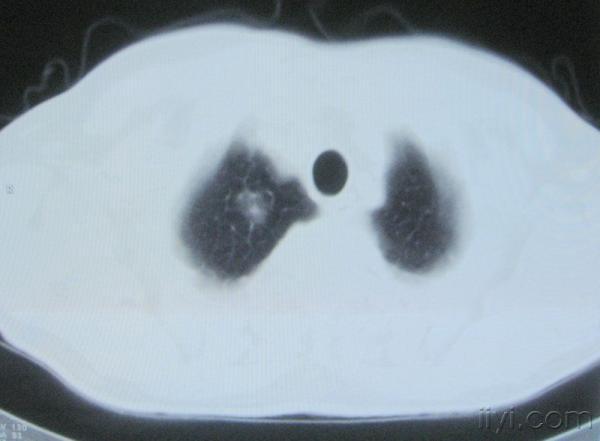

男。60岁,胸片示支气管炎治疗后复查CT。

根据位置考虑应该是淋巴结,密度不均,是因为肿大的淋巴结中心液化坏死

你指那个肯定是淋巴结,中央系坏死,这很常见,特别在双侧腹股沟会经常看到。这个双侧腋窝及纵隔见多发小淋巴结征。

应该是淋巴结没问题的,中心液化坏死是有这种情况的~~胸科常见到